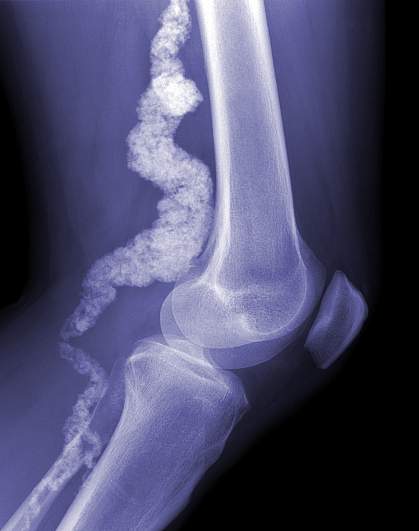

Scientists have discovered a genetic cause for a rare disorder that leads to calcium deposits in arteries in the lower half of the body and in the joints of patients' hands and feet. The culprit is a mutation in the gene encoding CD73, a protein that normally helps to prevent calcium buildup. The researchers hope that understanding the basis for this disease, which they call arterial calcification due to deficiency of CD73 (ACDC), will help them find a cure.

MRI and X-rays showed that members of the 2 families all had calcium buildup in arteries in the lower half of their bodies, but not around their hearts. In one family, 5 siblings but neither parent was affected by the disorder. The researchers suspected that symptoms might be due to a recessive gene variant. Recessive variants only show their effects when found in both copies of the gene.